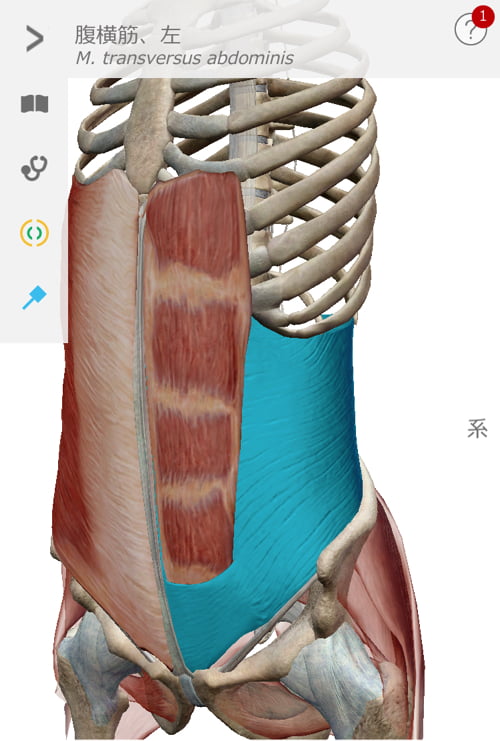

腰ではなく腹筋関連の硬直が大きな原因の1つ

まずはお腹周りから施術して行きます。

ぎっくり腰なのにお腹?と思うかも知れませんが

これらの筋肉が硬直して腰を前に引っ張り出してしまい

腰周りに歪みが出来たりズレが出来たりして痛みが発生するのです。